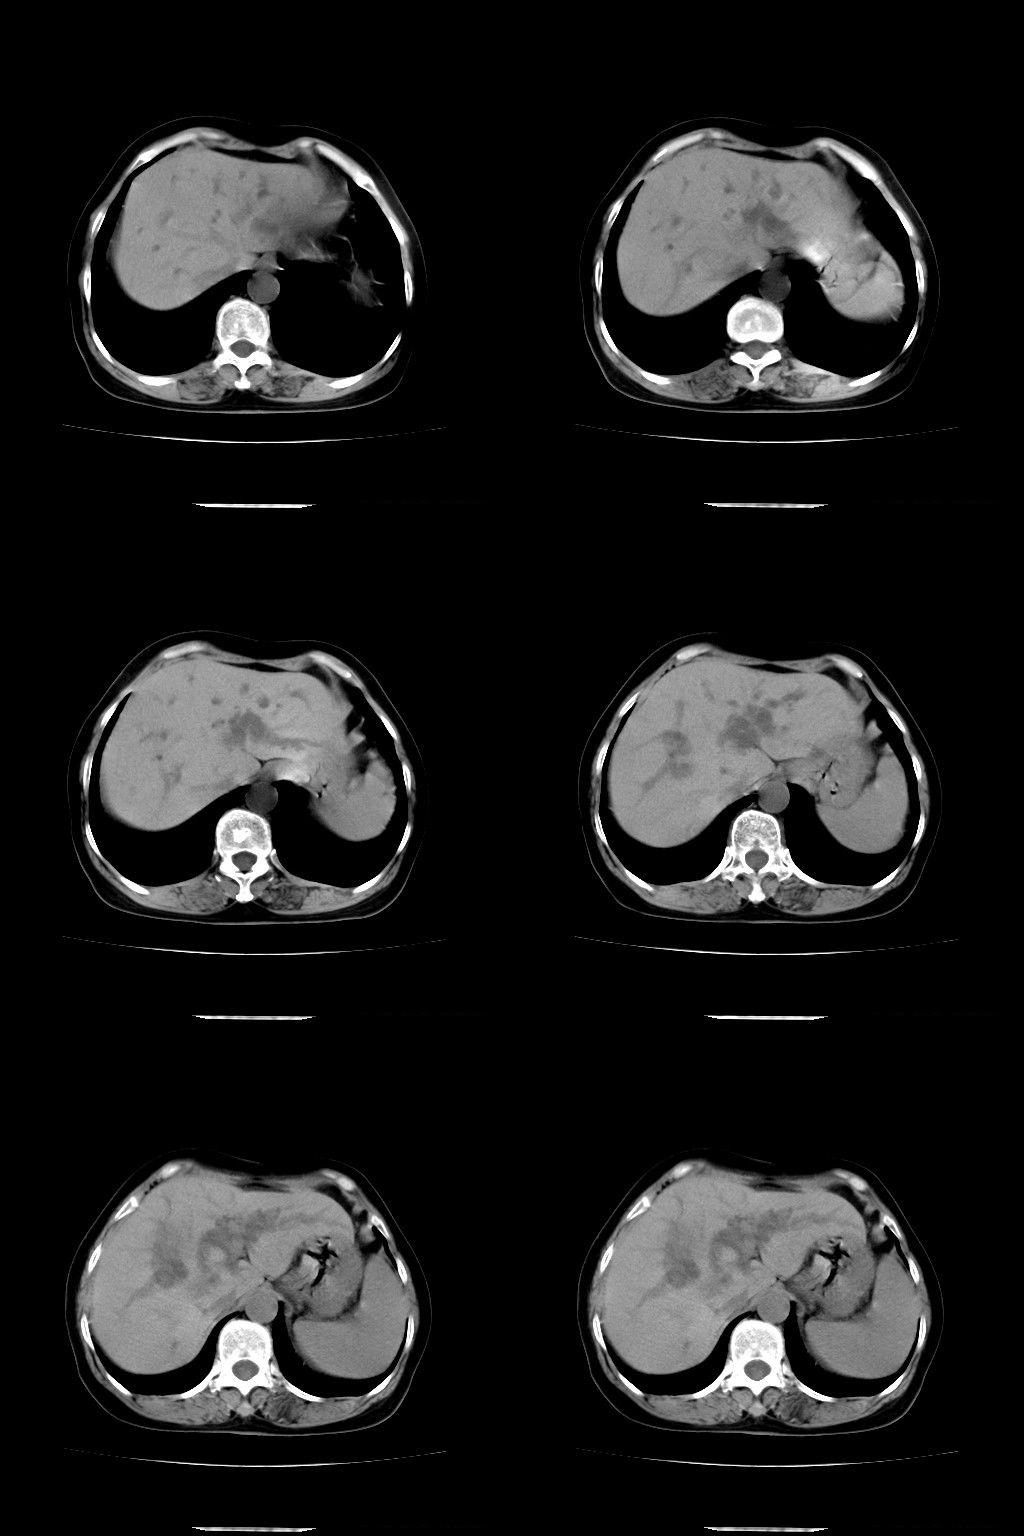

以下是引用余辉在2009-1-22 8:49:00的发言:[br]平扫肝内胆管扩张,右肝前叶球形低密度影,边缘较清楚,胆囊壁增厚,内可见较大高密度影,胆总管内亦可见高密度影,胰头区结构欠清。[br]增强动脉期见右肝前叶球形变灶明显增强,边缘见环状低密度区。胆囊见高密度影无增强,胆总管明显扩张,内见块状高密度影,周围环以低密度区,边界清楚。[br]静脉期见右肝前叶病灶持续增强,密度较动脉期增高。[br]考虑1胆囊及胆总管结石伴梗阻性胆系扩张,胆囊胆管炎。[br] 2右肝前叶占位性病变,强化规律符合胆管细胞癌,建议结合其他检查协诊